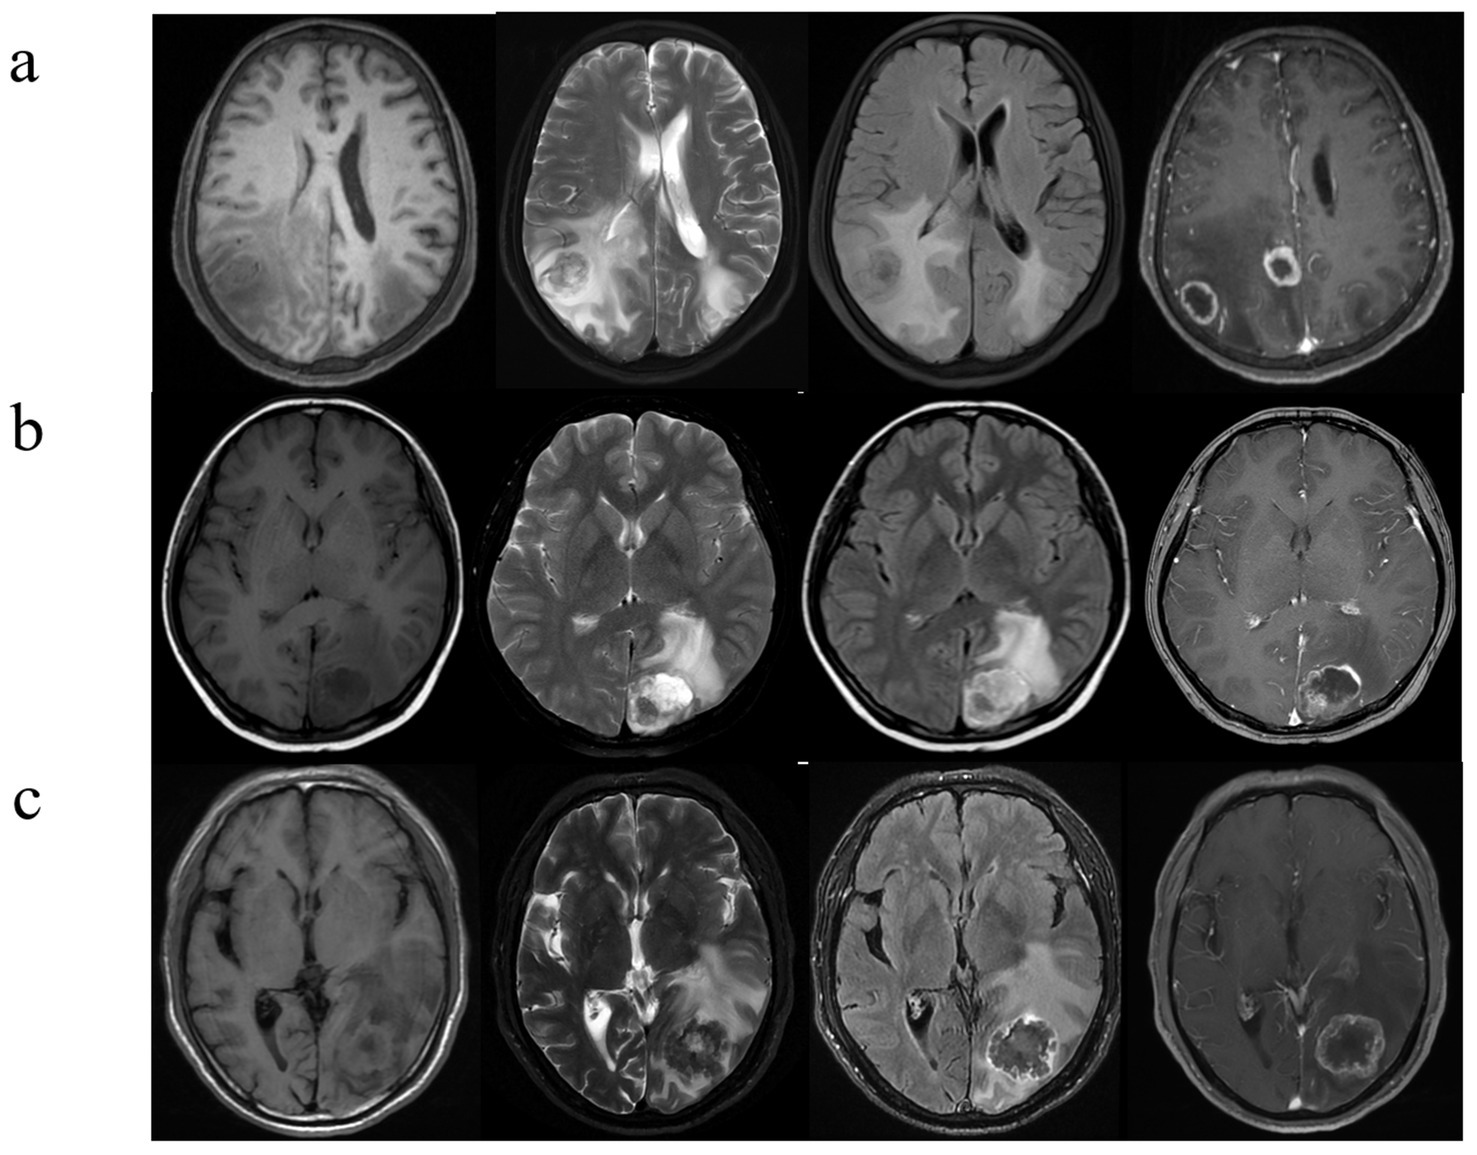

In all three cohorts, six clinical and MR features exhibited statistically significant differences (all p < 0.05; Table 1). Among the three cohorts of LC, BC, and GI, the highest proportion of female patients was observed in the BC cohort, with a statistically significant difference (p < 0.05). There were no statistically significant differences observed in age distribution, lesion size, or volume (p > 0.05). Patients with BM from three distinct primary sites frequently present with multiple intracranial lesions, often accompanied by peritumoral edema (p > 0.05). BMLC predominantly localize supratentorially (176 [72.1%]), typically appearing as round, nodular lesions (182 [74.6%]), with enhancement patterns commonly characterized by peripheral rim enhancement (207 [84.8%]) and infrequent cystic degeneration/necrosis (56 [23.0%]). Conversely, BMBC may also occur in the infratentorial compartment (57 [42.2%]), displaying lobulated, multi-nodular fusion morphology (82 [60.7%]), heterogeneous enhancement post-contrast (95 [70.4%]), and more frequent internal necrosis/cystic degeneration (81 [60.0%]). BMGiT may exhibit a typical low signal intensity on T2-weighted imaging (26 [43.3%]) (p < 0.05). Figure 3 illustrates representative cases of BM from different primary sites on MRI.

Figure 3

Brain metastases with atypical MRI findings. (A) A 73-year-old man with NSCLC. Multiple hyperintense nodules are observed in the bilateral occipital lobes and lateral ventricular trigones on T2WI and FLAIR sequences, accompanied by significant perilesional brain edema, and there is evident ring enhancement on CE- T1WI. (B) A 53-year-old woman with a history of breast cancer surgery 3 years ago presents with cystic-solid, lobulated nodules located beneath the cortical layer of the left occipital lobe. The nodules exhibit mixed high signal intensity on both T2WI and FLAIR sequences, along with surrounding peritumoral edema. CE- T1WI reveals significant and heterogeneous enhancement. (C) A 42-year-old man, diagnosed with signet ring cell carcinoma on gastroscopy, presents with severe headaches. T2WI shows a low signal intensity nodule in the left occipital lobe, with unclear borders. The lesion demonstrates central hypointensity and peripheral hyperintensity on FLAIR sequences, accompanied by significant peritumoral edema. Additionally, there is heterogeneous ring enhancement surrounding the lesion.